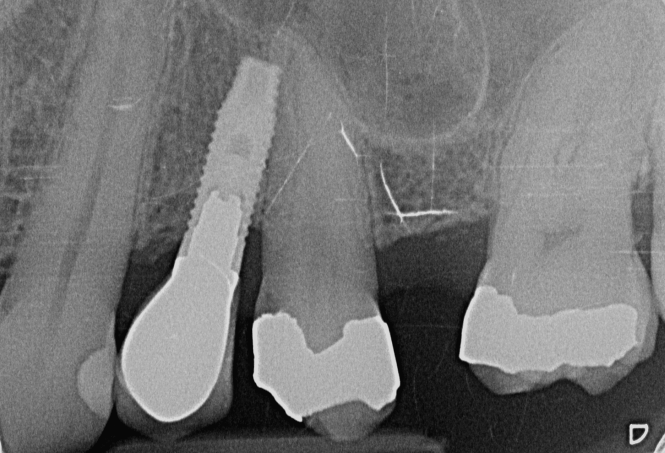

Implante desconocido y tornillo incompatible

Hola compañer@s necesito vuestra ayuda. Este paciente tiene movilidad en el puente implante-diente, mis destornilladores de 1.20, 1.25, 0.90 y dinámico no son compatibles. No sé ni qué implante es [...]

implante de conexión trilobular tipo Nobel o implant direct de color amarillo pero con un tornillo pasante de multiin muy largo gracias por vuestra ayuda

creo que el 21 es straumann tissue level pero os agradeceria que me lo confirmaseis. Tampoco tengo idea de cual es el 1.1. necesito una ayuda profesional gracias de antemano